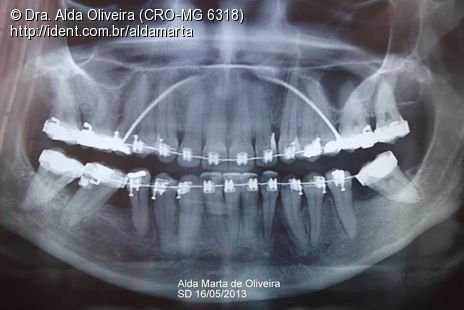

Compensação em Classe Iii

Caso clínico, 05 de Jul de 2012

Fico tão empolgada com a evolução desse meu caso de orto que não resisto e venho aqui dividir com vocês minha satisfação!

Início: 18/08/2010

Fotos do caso